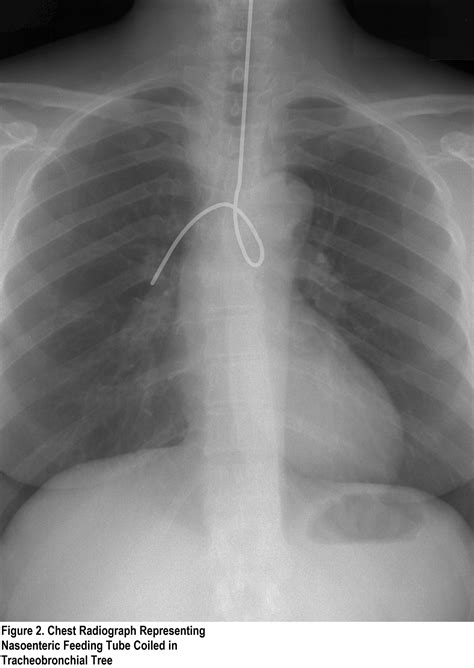

Never rely on a single method to confirm Nd tube placement. Because of the risk of placing the tube into the lungs, multiple verification methods are required before initiating any feeds or medications.

Radiography (X-Ray) The gold standard. An abdominal or chest X-ray provides definitive visualization of the tube tip in the stomach.

⚠️ Note: Always wait for definitive radiographic confirmation before using the tube for feeding or medication administration, especially in unconscious or sedated patients.

• Aspiration Pneumonia: Occurs if the tube is in the trachea or if gastric contents reflux.